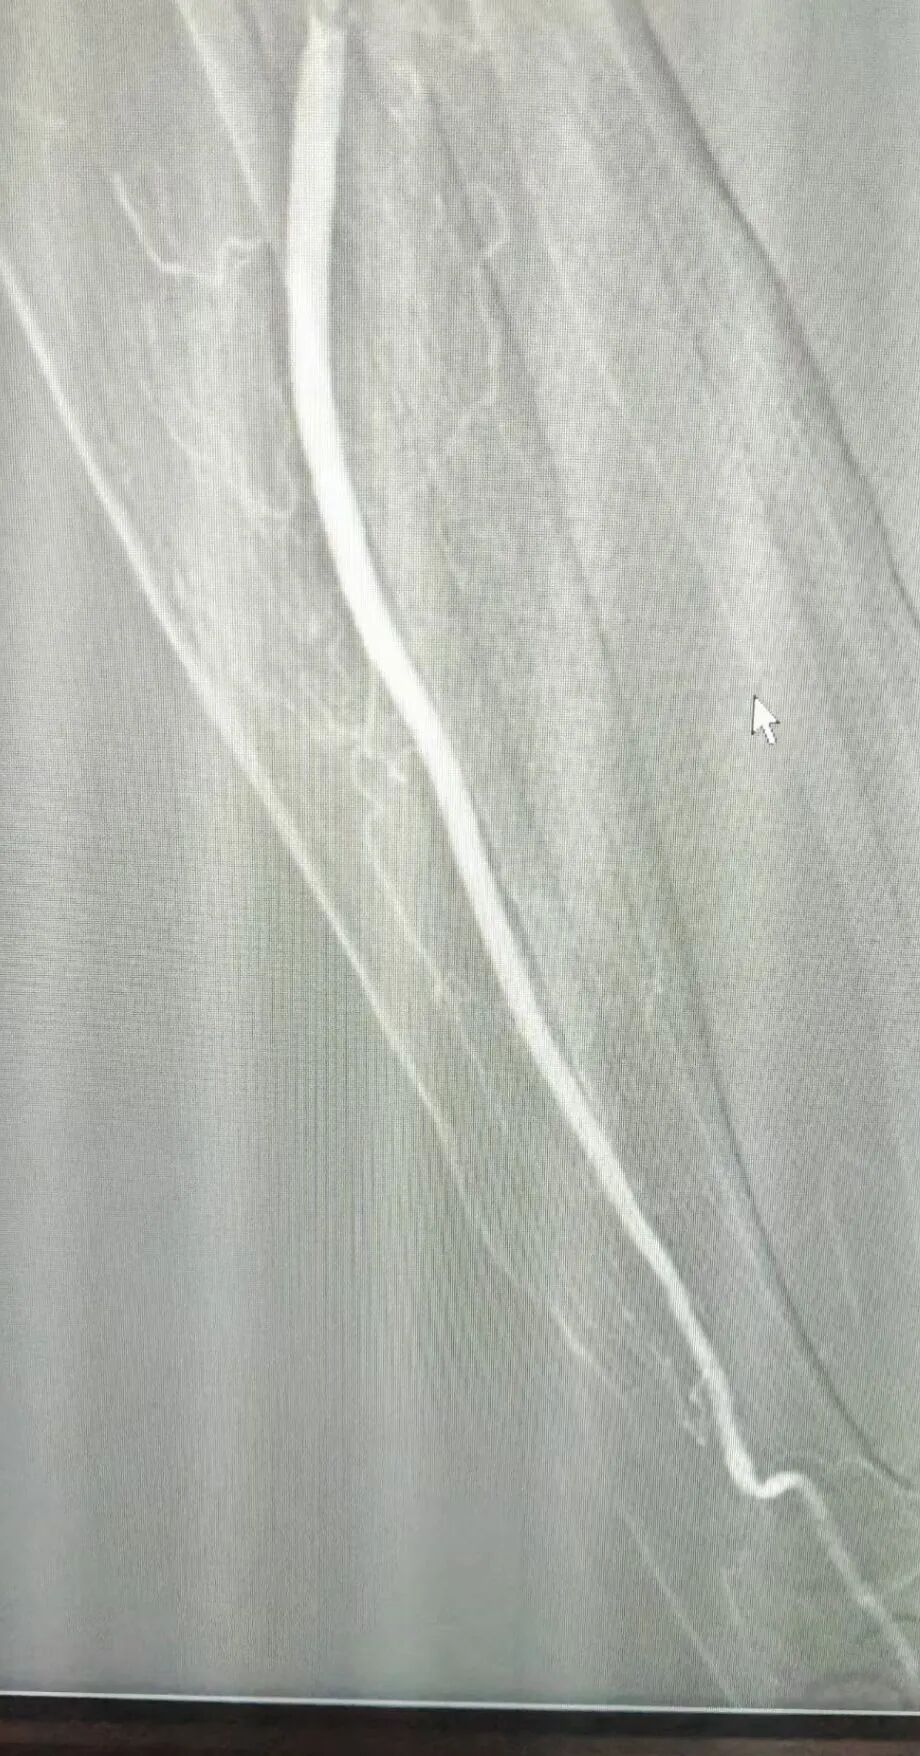

检查结果显示:左侧桡动脉纤细,左侧尺动脉未见显影,这意味着张爷爷的左侧尺动脉已经完全堵塞。情况十分危急,张爷爷被紧急送往手术室,急诊科主任兼介入中心主任陈向成、外二科副主任医师左敏毅以微创介入的方式对堵塞的尺动脉进行取栓和溶栓治疗。

随着血管里的血栓被逐渐清除,张爷爷左手的血液循环慢慢恢复正常,手指颜色也从苍白变得红润起来。